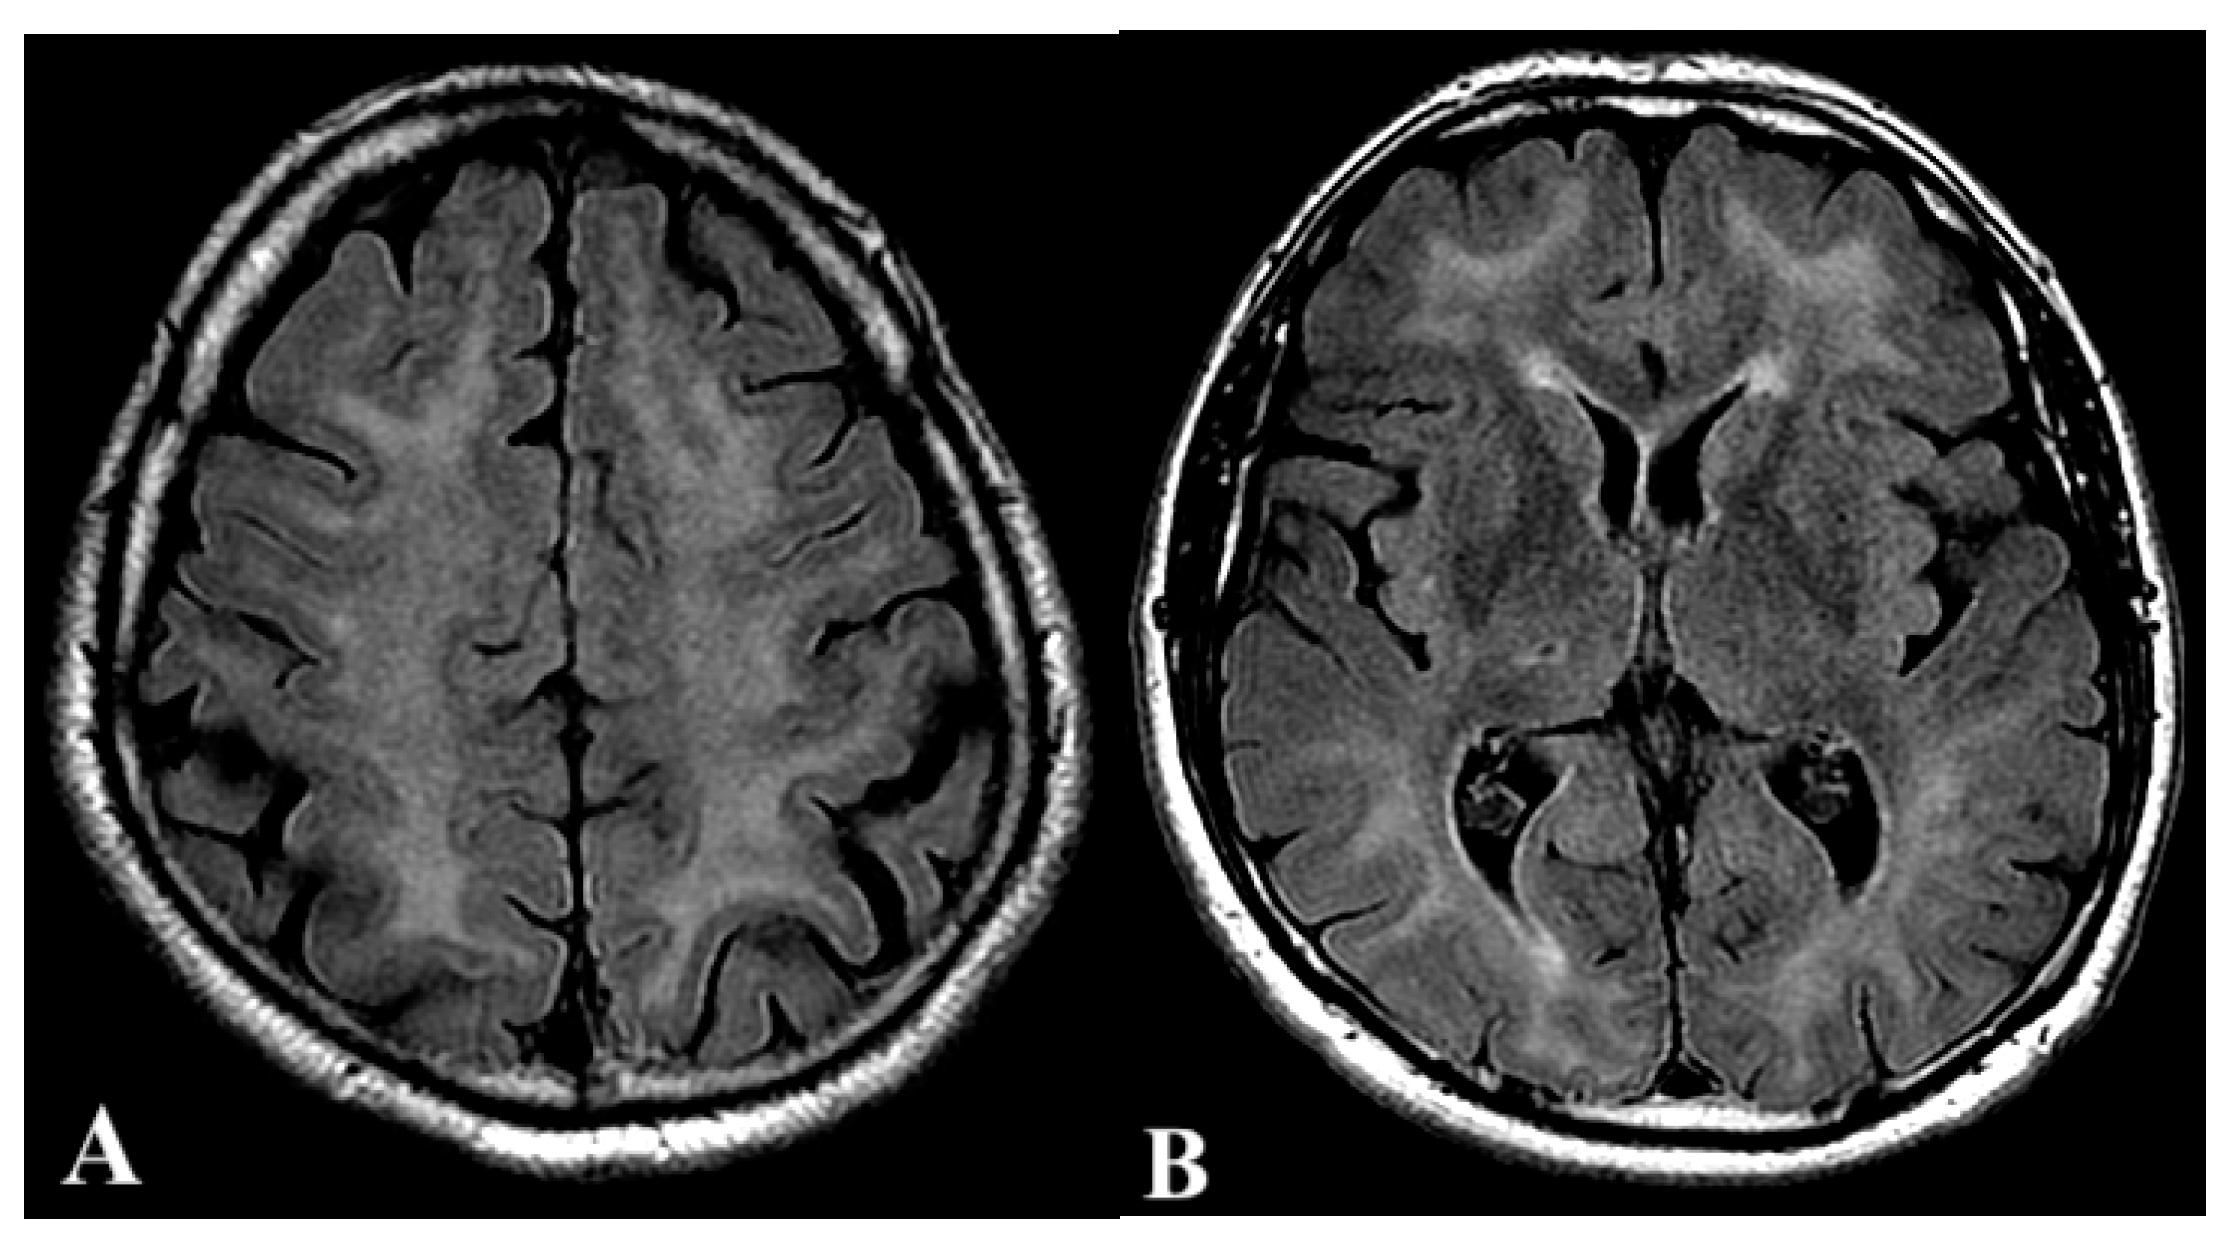

2.1. First Case

2.2. Second Case